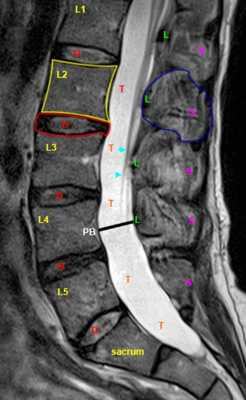

МРТ позвоночника. Сагиттальная Т2-взвешенная МРТ, срединный срез поясничного отдела. Показана нумерация позвонков, измерения позвоночного канала (черная линия). Т- дуральный мешок с ярким ликвором. L- желтая связка. Sacrum - крестец. D - межпозвоночный диск. Голубым выделен остистый отросток, желтым - тело позвонка, Голубые точки - ход корешков.

После того, как появилась ясность в способе получения МРТ изображений позвоночника, надо понять какие анатомические структуры видны. Счет позвонков ведется разными способами - сверху от зубовидного отростка С2 (осевой позвонок), от бифуркации трахеи Т5 ( пятый грудной, с погрешностью на 1 позвонок) или снизу от L5 (последний поясничный), также не исключена погрешность на 1 позвонок в связи люмбализацией или сакрализацией. Анатомия позвоночника в МРТ изображении представлена в нашей другой статье. На серии сагиттальных Т2-взвешенных МРТ позвоночника видны асе основные структуры, причем удается проследить ход корешков конского хвоста. В поясничном отделе он идет под углом вниз и выходит через межпозвоночное отверстие нижележащего позвонка. Аксиальные (поперечные) МРТ срезы всегда делаются вдоль межпозвоночного диска, то есть с учетом нормальных или патологических изгибов позвоночника. Они наиболее удобны для оценки состояния дугоотростчатых суставов. При МРТ позвоночника в поперечной плоскости МРТ срезы часто делают на разных уровнях для лучшей визуализации состояния корешков по их ходу - в дуральном мешке, затем боковом кармане дурального мешка, далее в межпозвоночном отверстии и, наконец, после выхода из него. Таким образом, в поперечном МРТ срезе позвоночника через межпозвоночное отверстие на поясничном уровне можно видеть отрезки сразу двух корешков - вышележащего на выходе из отверстия, и нижележащего в боковом кармане.